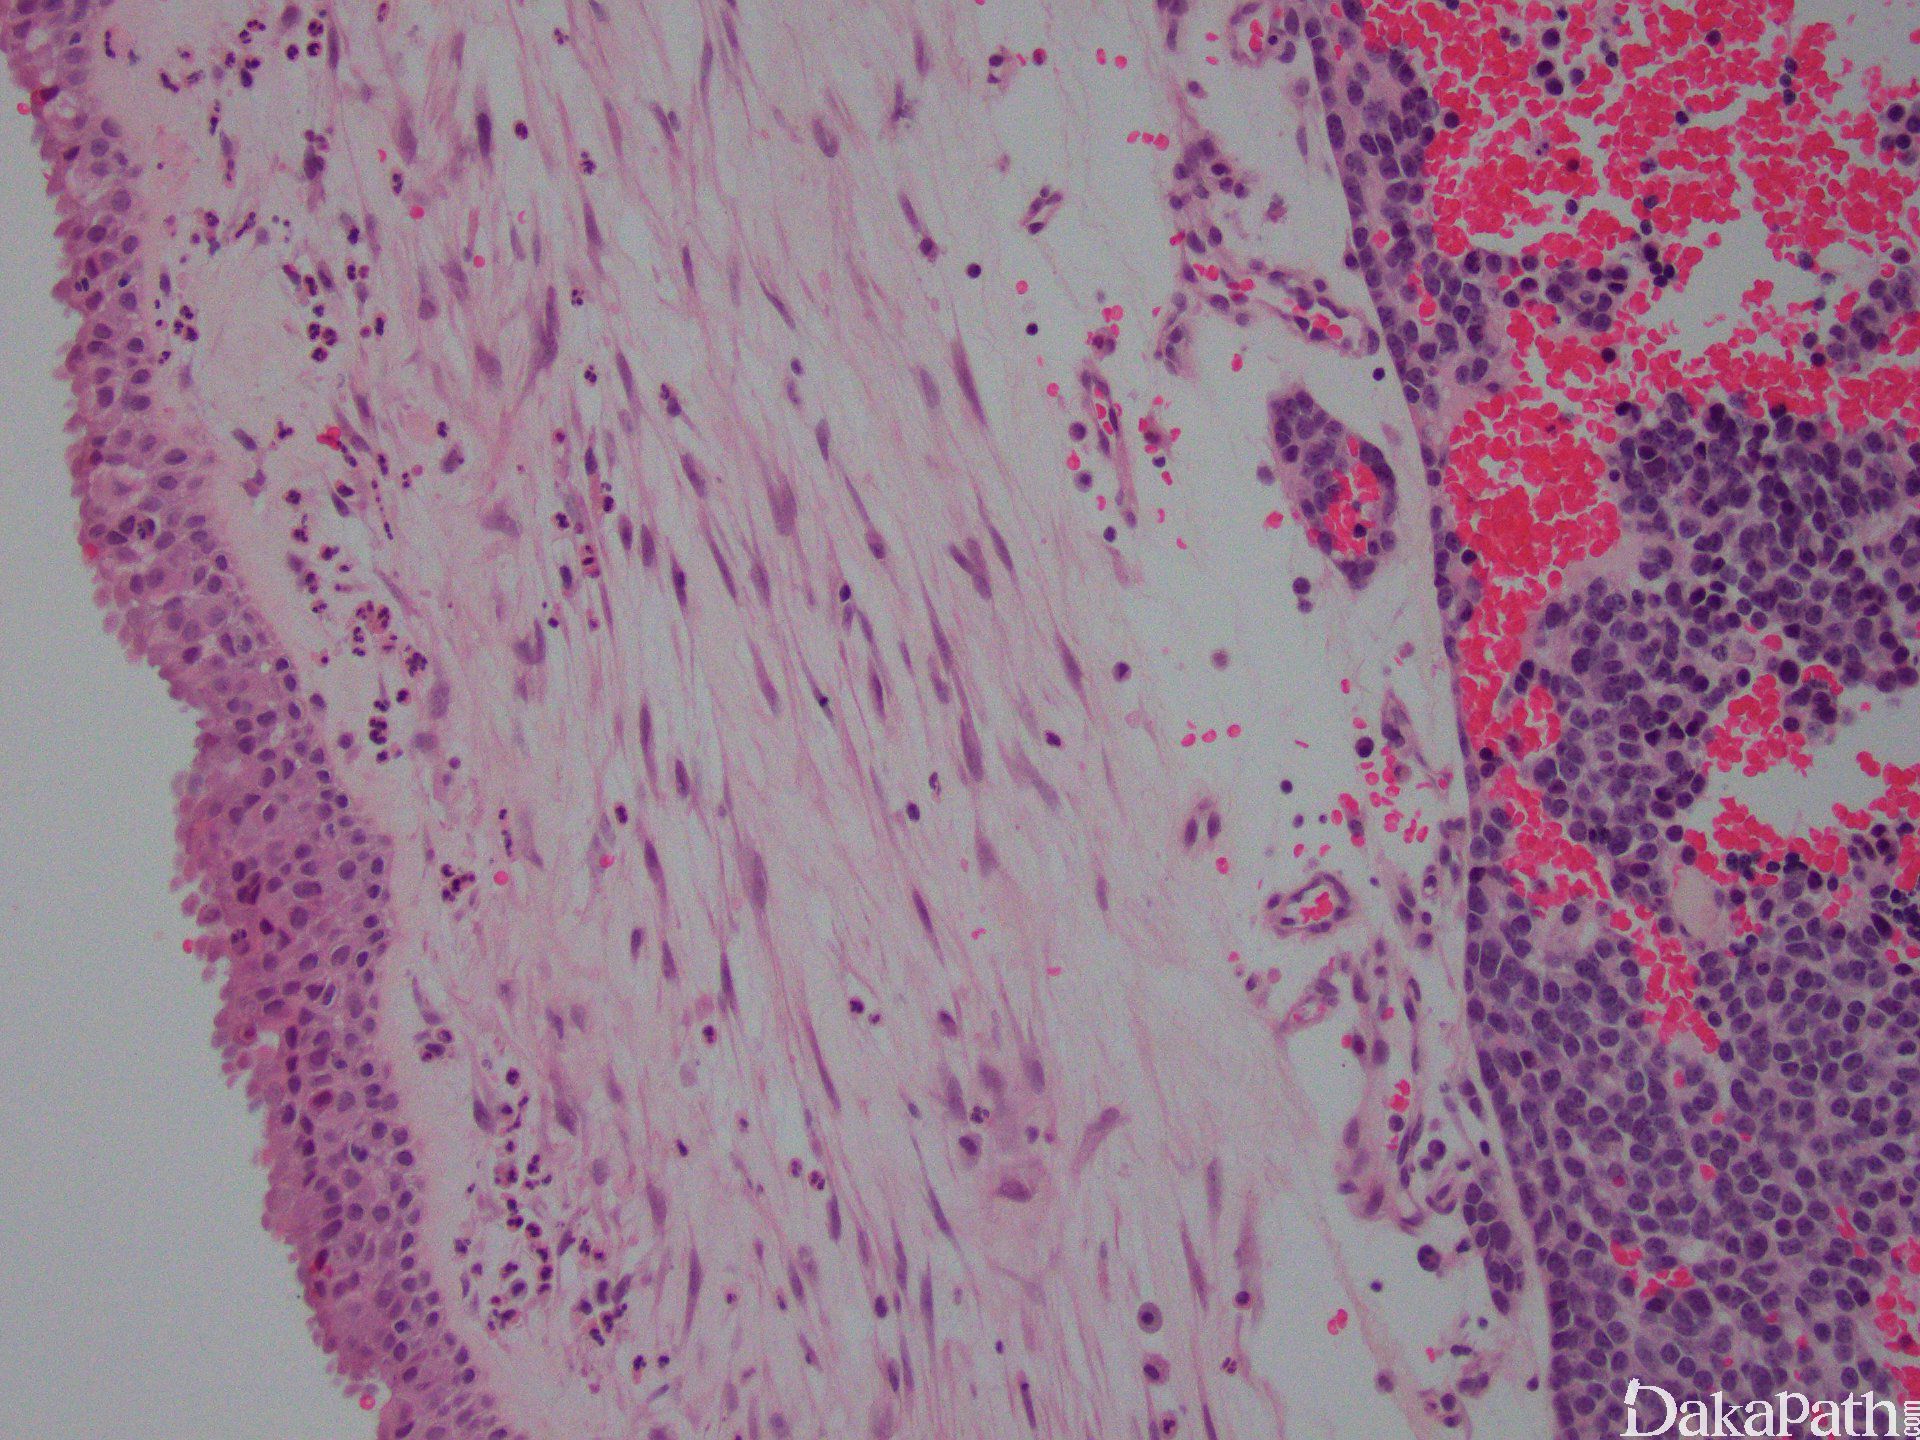

组织学改变基于分化成程度不同而呈不同,原始神经母细胞分叶状排列(不管分级如何)。叶状结构之间富于纤维血管间隔,支持细胞常位于细胞巢周边。

肿瘤细胞呈经典小圆蓝细胞,比成熟淋巴细胞稍微大一些,核浆比高,小而一致的胞核伴细致、椒盐样染色质分布,胞核比较小或缺席。细胞呈合胞体样。可见中央为神经丝状物构成的菊形团(Homer Wright)。

可见两种菊形团形式:假菊形团 (Homer Wright)及真菊形团(Flexner-Wintersteiner)。假菊形团见于 30%的病例,肿瘤细胞栅栏状、套样围绕在神经丝样、水肿样神经基质的周围,可见于 1 级或 2 级。真菊形团见于 5%的病例,中空导管样伴非纤毛样柱状细胞,可见与 3 级或 4 级。围血管性菊形团没有诊断价值。

表面上皮完整。